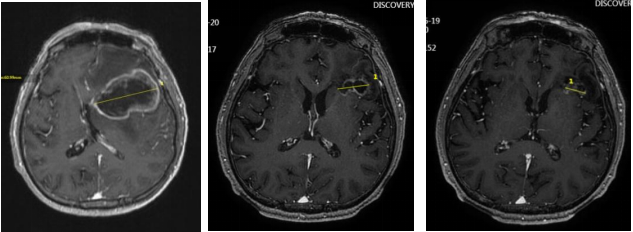

● 2025年3月20日头颅MRI增强:左侧额叶占位及周围水肿范围较2025年1月16日明显缩小。总体评效:PR(缩小53%)。

● 2025年6月19日复查头颅MRI增强:左侧额叶占位及周围水肿范围较2025年3月20日缩小。总体评效:PR(缩小70%)。

头颅增强MRI(左:2025年1月16日;中:2025年3月20日;右:2025年6月19日)